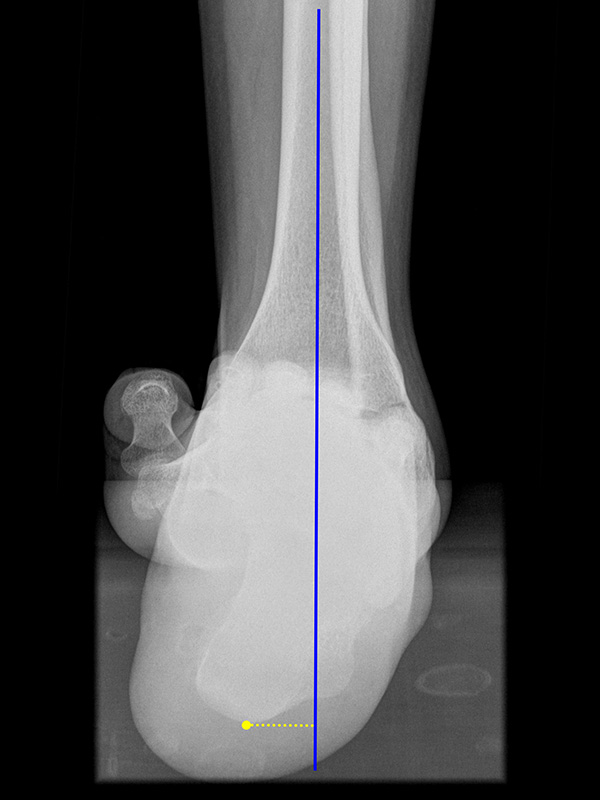

Saltzman Rückfußachsaufnahme (Hindfoot alignment view)

Rückfuß-Alignement-Aufnahmen sind eine wichtige Ergänzung zur Diagnostik von Kalkaneusfehlstellungen (Varus und Valgus), sowie bei der Planung von Rückfußkorrekturen 14.

Kennzeichen des Röntgenbildes:

• Markieren der Tibiaachse mit Verlängerung nach distal.

• Der funktionelle Hebelarm des Kalkaneus errechnet sich aus der Distanz zwischen der Tibiaachse und dem am weitesten plantar gelegenen Punkt des Kalkaneus.

• Liegt der tiefste Punkt des Kalkaneus medial der Tibiaachse, handelt es sich um eine Varus-Stellung, liegt er lateral, um eine Valgus-Stellung.

• Norm: Auftrittspunkt 3,2 ± 8 mm medial der Tibiaachse 14.